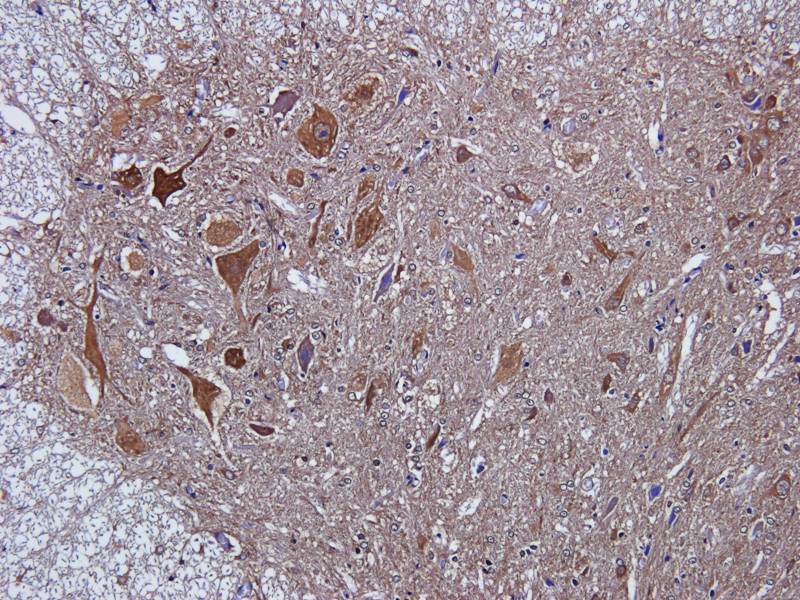

IHC staining of FFPE human brain with Ubiquitin antibody (clone PBQN-1). Required HIER: boil tissue sections in pH9 10mM Tris with 1mM EDTA for 10-20 min followed by cooling at RT for 20 min.